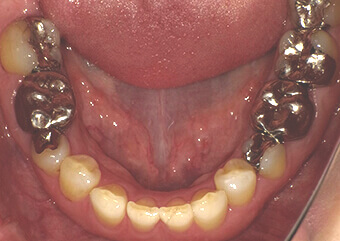

被せ物 施術前

奥歯の金属のかぶせ物、詰め物をセラミックスで再修復しました。セラミックスは欠けやすい(壊れやすい)と言われたのは昔の話で、噛む力にも耐えうる十分な強度を持ち合わせています。周りの色調に合わせるための色付けを省いて作製することで、コストを抑えることもできます。